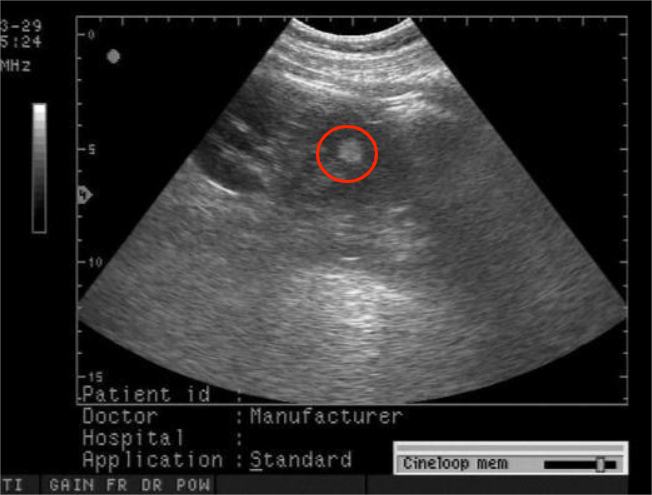

肾错构瘤属于常见的肾良性肿瘤,超声可发现边界清晰的强回声光团,无声影。由异常增生的血管、平滑肌和脂肪组成。

肾错构瘤体积不大时多无症状,较大时可因挤压周围组织和腹腔脏器,引起上腹腹胀感等不适。超声检查可见边界清晰的强回声光团,无声影,多见于直径0.5-2厘米的较小肿瘤。当肿瘤内部多次出血时,可见高、低混合回声肿块,为“洋葱样”图形。